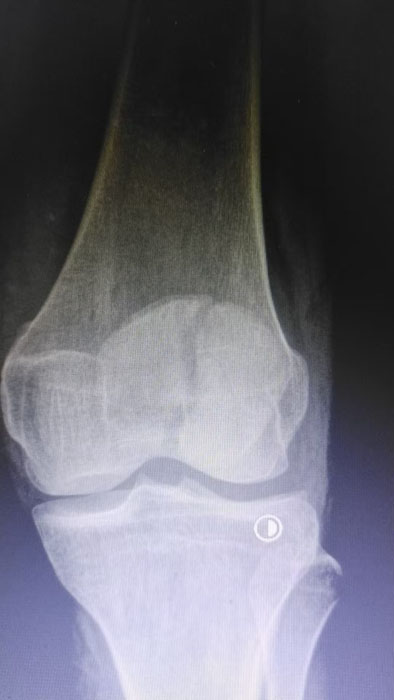

该患者因意外外伤导致髌骨骨折后,紧急前往何店镇中心卫生院就诊。该院外科医护团队迅速响应、规范处置,第一时间为患者完善各项术前检查,全面细致评估患者身体状况及骨折伤情,精准把握手术指征。为最大限度保障手术安全与治疗效果,切实减少患者往返城区医院的奔波之苦,降低就医成本,该院立即启动医共体专家协作机制,正式向曾都区人民医院申请专家技术支持。接到申请后,徐三军主任快速响应、主动下沉,带着丰富的临床经验和精湛的手术技术赶赴卫生院,与该院外科医护团队深入研讨,结合患者具体病情制定个性化手术方案,细致梳理术前各项准备工作,为手术顺利开展筑牢坚实基础。

手术现场,徐三军主任凭借多年积累的临床经验和娴熟的手术技巧,精准完成骨折复位、钢板内固定、伤口缝合等一系列关键操作,动作规范流畅、精准高效,最大限度减少手术创伤。该院外科医护团队全程密切配合、协同发力,严格按照手术规范操作,全程严密监测患者心率、血压等生命体征,及时应对术中各类突发情况,全力保障手术安全。此次手术全程顺利,术中出血量少,患者生命体征始终平稳,术后患者顺利安返病房,为后续康复治疗奠定了坚实基础。